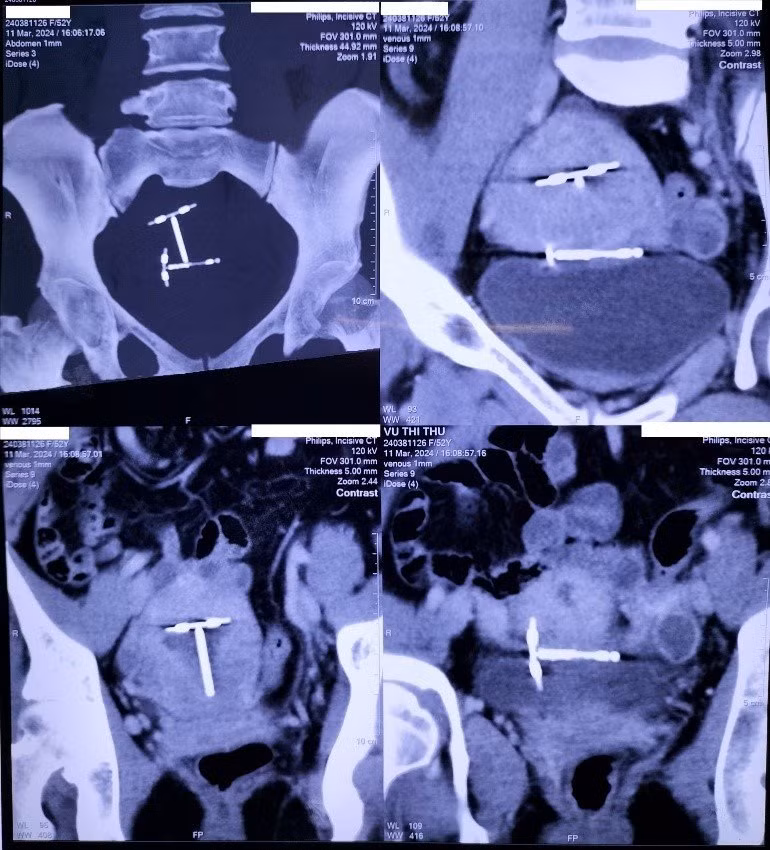

Thời gian gần đây, xuất hiện tình trạng đau bụng dưới nhiều, bệnh nhân T. quyết định khám tại Bệnh viện Quân y 175, kết quả chụp CT Scanner ổ bụng chẩn đoán có 2 vòng tránh thai: 1 vòng nằm đúng vị trí trong tử cung, 1 vòng lạc chỗ trong ổ bụng nằm giữa tử cung và bàng quang.

Theo BS Trang, đối với trường hợp bệnh nhân T, khi vào ổ bụng có 1 nhánh ngang của vòng cắm vào mặt trước đoạn dưới cơ tử cung, 1 nhánh ngang nằm trong phúc mạc phủ mặt trước tử cung sát với trần bàng quang, thân vòng nằm ngang trong lớp cơ đoạn dưới cơ tử cung.

![]() |

| Hình ảnh siêu âm ổ bụng bệnh nhân cho thấy hình ảnh vòng tránh thai trên màn hình. |